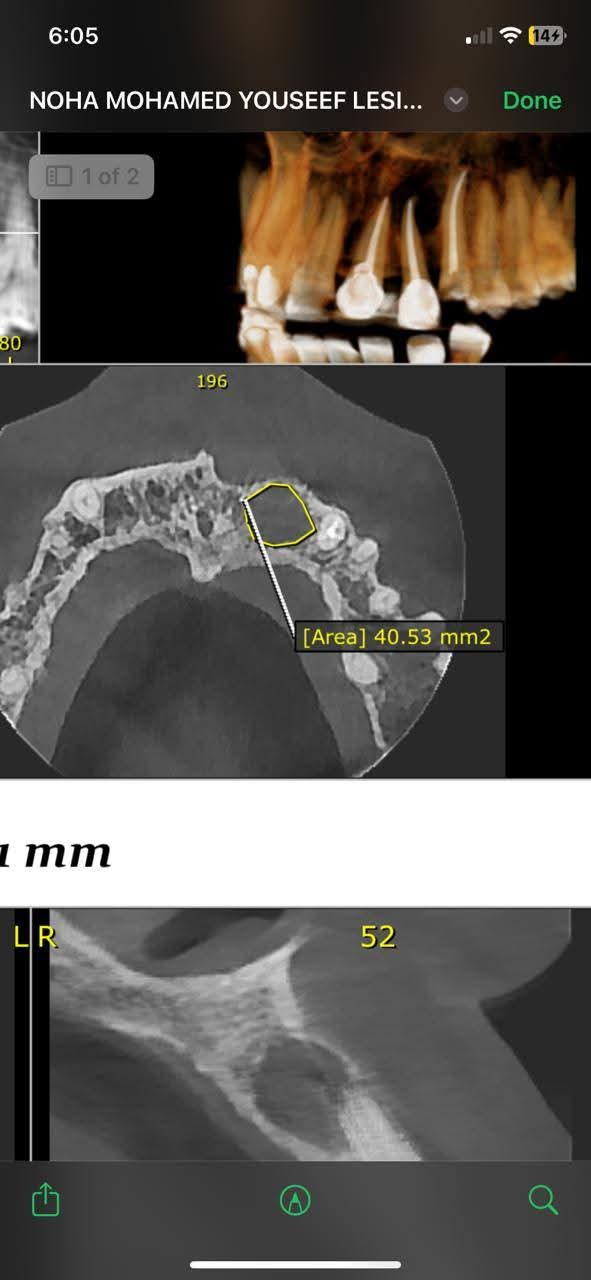

أعلنت مديرية الشؤون الصحية بسوهاج نجاح فريق متميز من أطباء الأسنان بمستشفى جهينة المركزي في إجراء عملية دقيقة لإزالة كيس مرضي تحت القاطع الأول والثاني يسار الفك العلوي لفتاة تبلغ من العمر 23 عامًا.

و استغرقت الجراحة نحو ساعة ونصف تحت التخدير الموضعي، وتمت بنجاح تام مع استئصال الكيس المرضي كاملًا، في سابقة تُعد الأولى من نوعها داخل المستشفى.